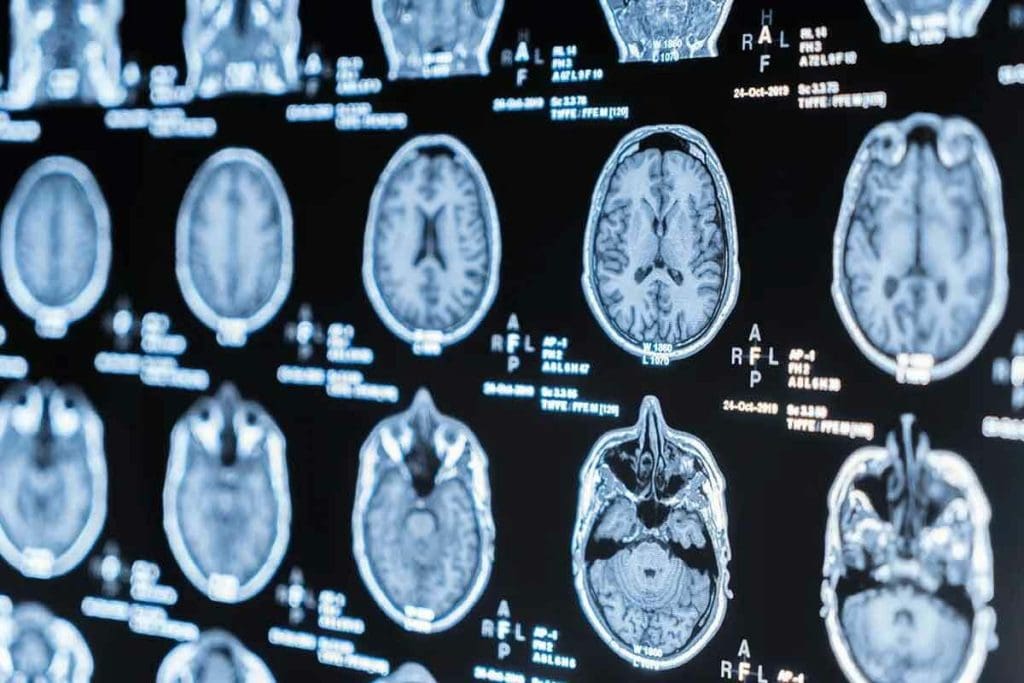

Do MRIs Show Broken Bones? Understanding How MRI Helps in Diagnosis

At Liv Hospital, we know that accurate diagnosis is key to effective treatment. Many patients ask, do MRIs show broken bones? While X-rays are commonly used to detect fractures, they can sometimes miss complex breaks or soft tissue injuries.

That’s where MRI technology becomes invaluable. MRI scans provide highly detailed images, helping doctors identify stress fractures, bone bruises, ligament tears, and joint injuries that X-rays might overlook. According to the Mayo Clinic, MRIs are especially effective in spotting tiny or hidden fractures.

Do MRIs Show Broken Bones? Understanding Capabilities

It’s important to know how MRI works for diagnosing broken bones. MRI technology has improved a lot. It can show detailed images of bones and soft tissues around them.

How MRIs Visualize Bone Structures

MRI scans use a strong magnetic field and radio waves to create detailed images. Unlike X-rays, MRIs show both bones and soft tissues. This is great for checking injuries, like fractures and soft tissue damage.